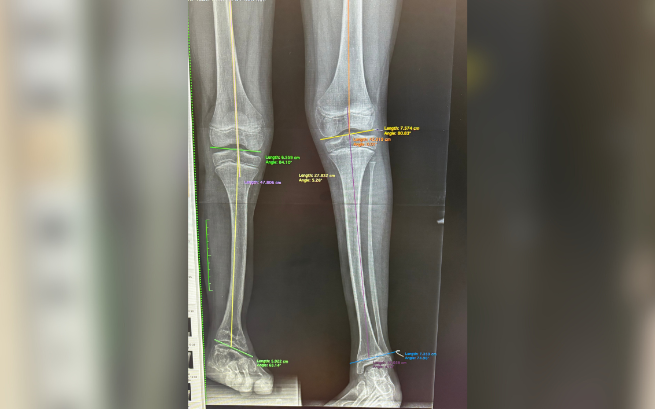

Dzięki wsparciu poprzedniej zbiórki jesteśmy już po pierwszym zabiegu wydłużania! Udało się wydłużyć nogę o 6 centymetrów! Po rehabilitacji Miki mógł już oficjalnie odrzucić kule i powoli wracać do formy.

Ale to jeszcze nie koniec walki. Czeka nas kolejna operacja wyciągnięcia płytki w kolanie. To kolejne koszty, ale jesteśmy ogromnie szczęśliwi, że zabieg się udał. Teraz musimy doprowadzić sprawę do końca. Bez Was nie bylibyśmy w tym miejscu.